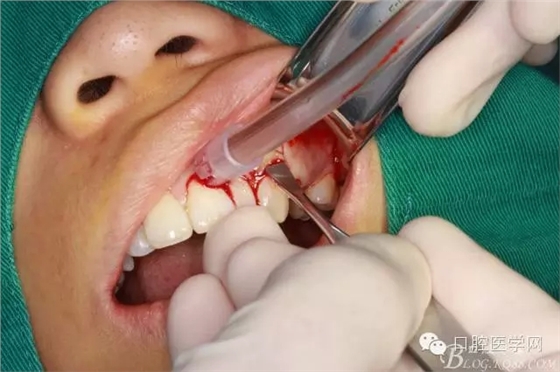

垂直切口

水平切口

翻全厚瓣(-)

翻全厚瓣(二)